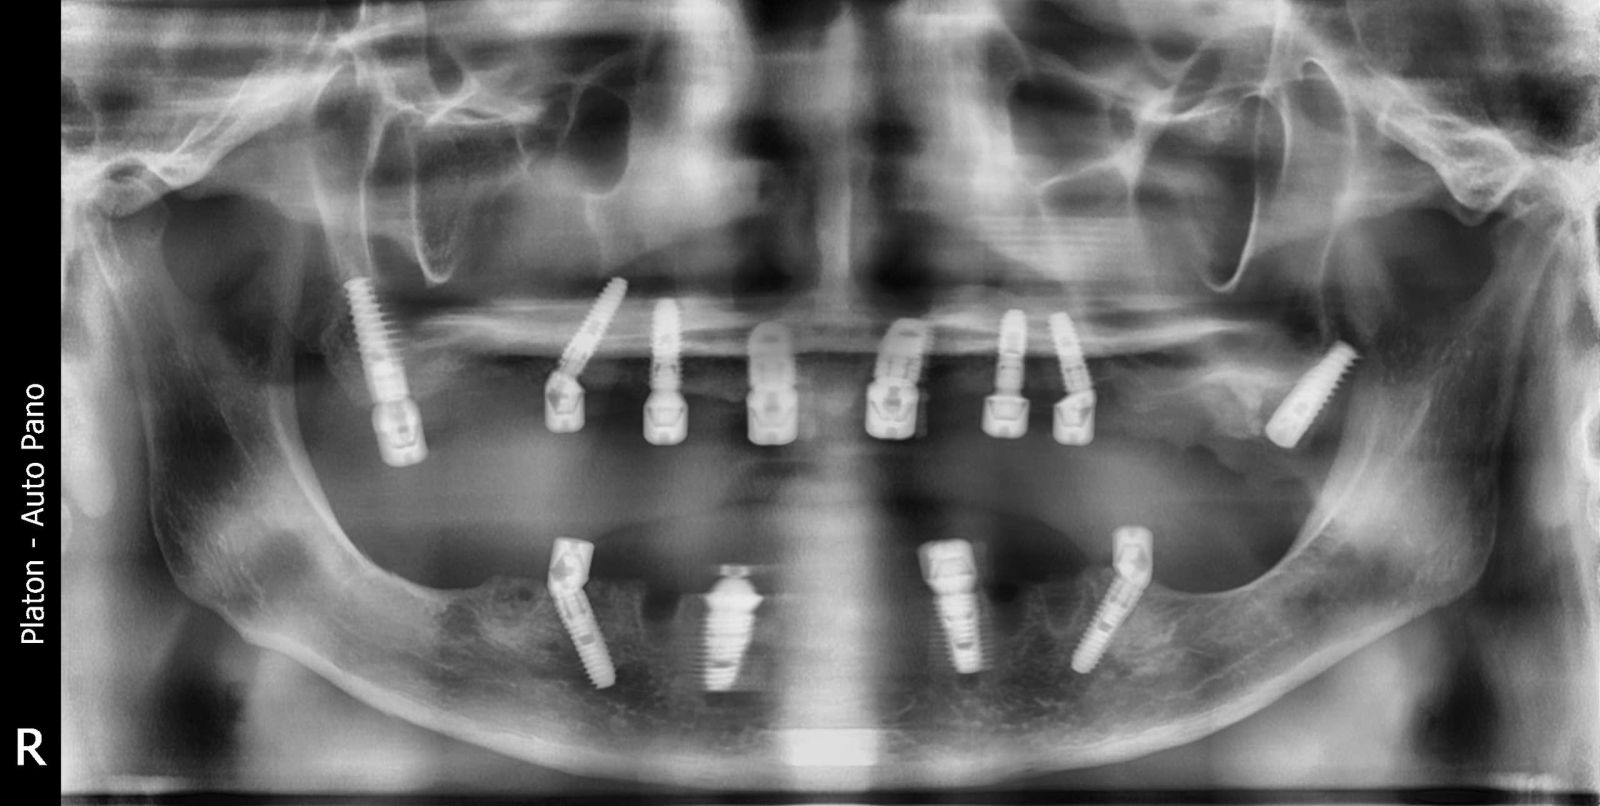

Sau khi được bác sĩ thăm khám, chụp phim 3D và lên kế hoạch điều trị cá nhân hóa, đội ngũ chuyên môn đã tiến hành đặt 6 trụ Implant chiến lược trên mỗi hàm, tạo nền vững chắc để phục hình cố định toàn bộ răng.

Phương pháp All-on-6 sử dụng 6 trụ Implant titanium cấy vào xương hàm, giúp:

Phân bổ lực nhai đều, tăng độ vững chắc.

Giảm số lượng trụ cấy nhưng vẫn đạt hiệu quả tối ưu.

Phục hình cố định toàn hàm trong thời gian ngắn.

Phù hợp cho người mất răng toàn hàm, tiêu xương nhiều hoặc lớn tuổi.